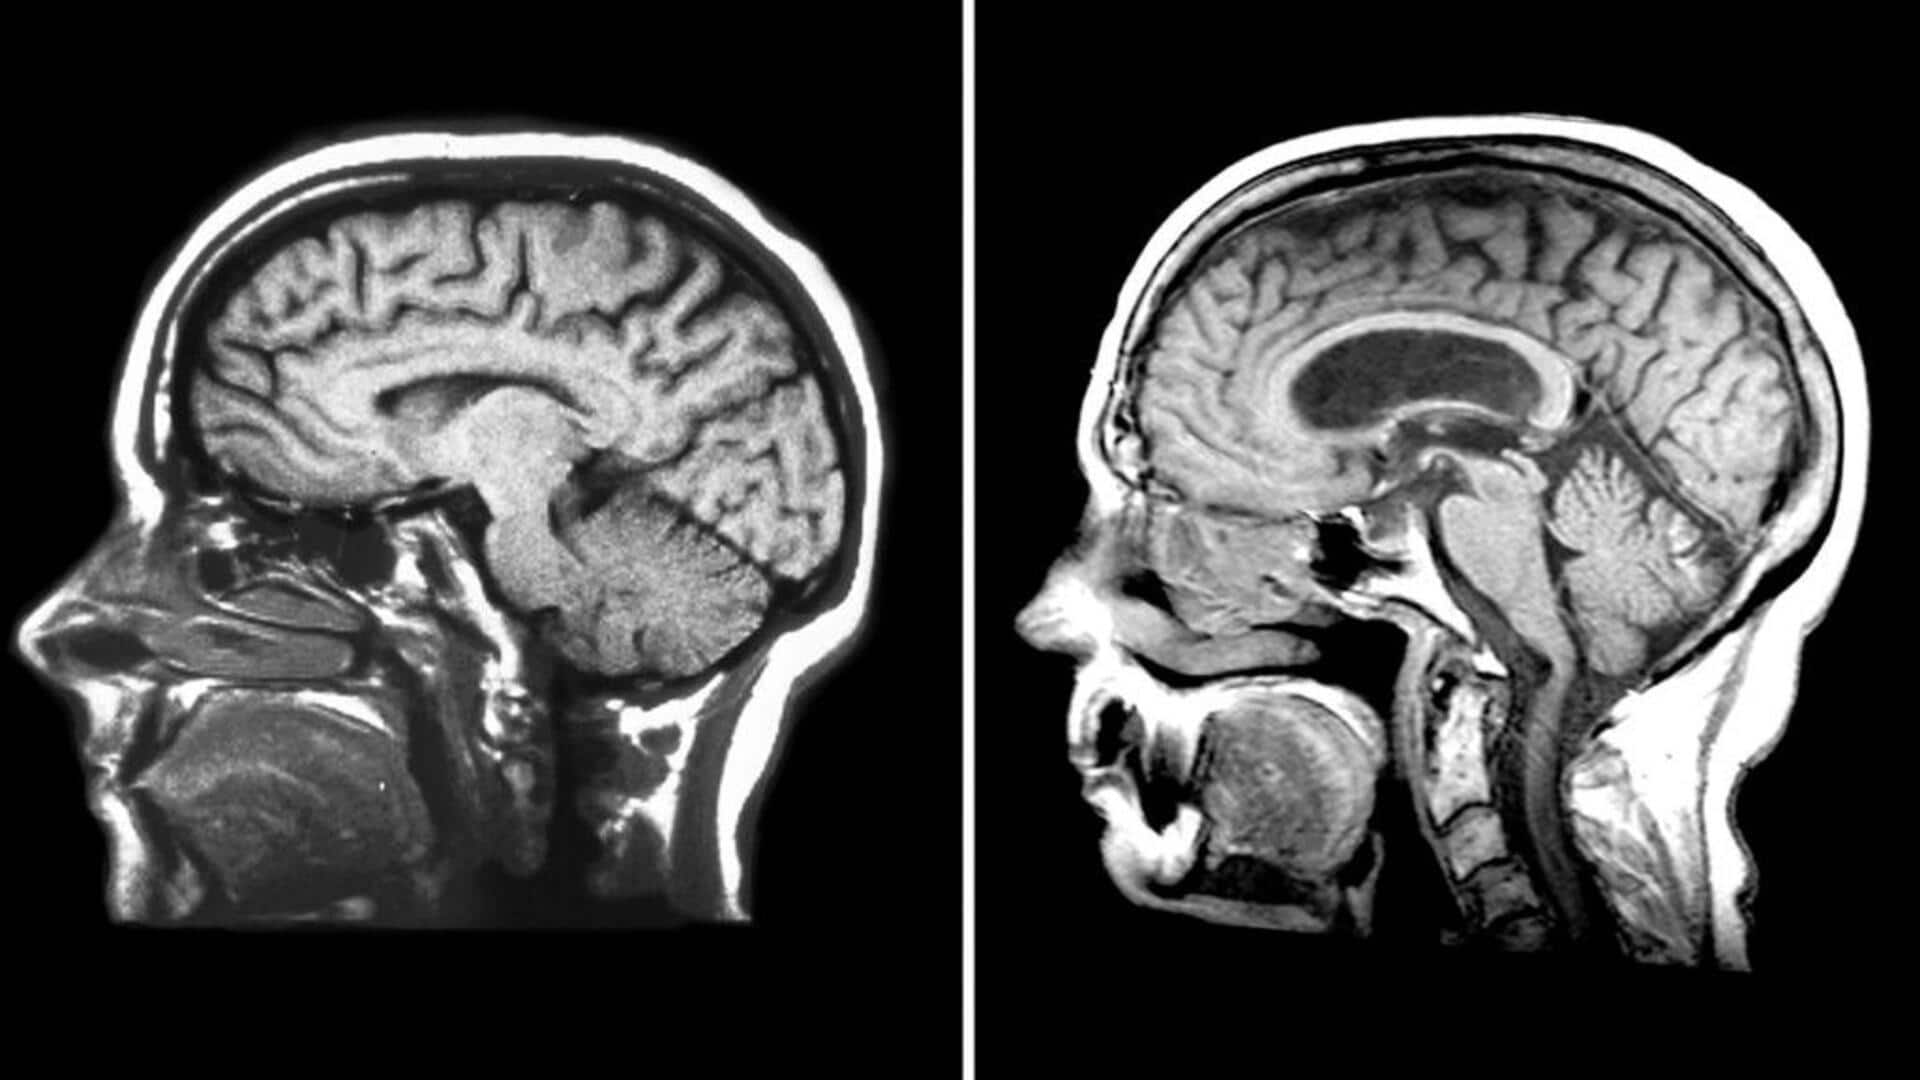

Cairan serebrospinal (CSF) sering kali dianggap hanya sebagai pelindung otak dan sumsum tulang belakang. Namun, cairan ini memiliki peran yang lebih kompleks dan penting dalam tubuh manusia. Artikel ini akan mengungkap lima fungsi tak terduga dari cairan cerebrospinal yang mungkin belum banyak diketahui orang.